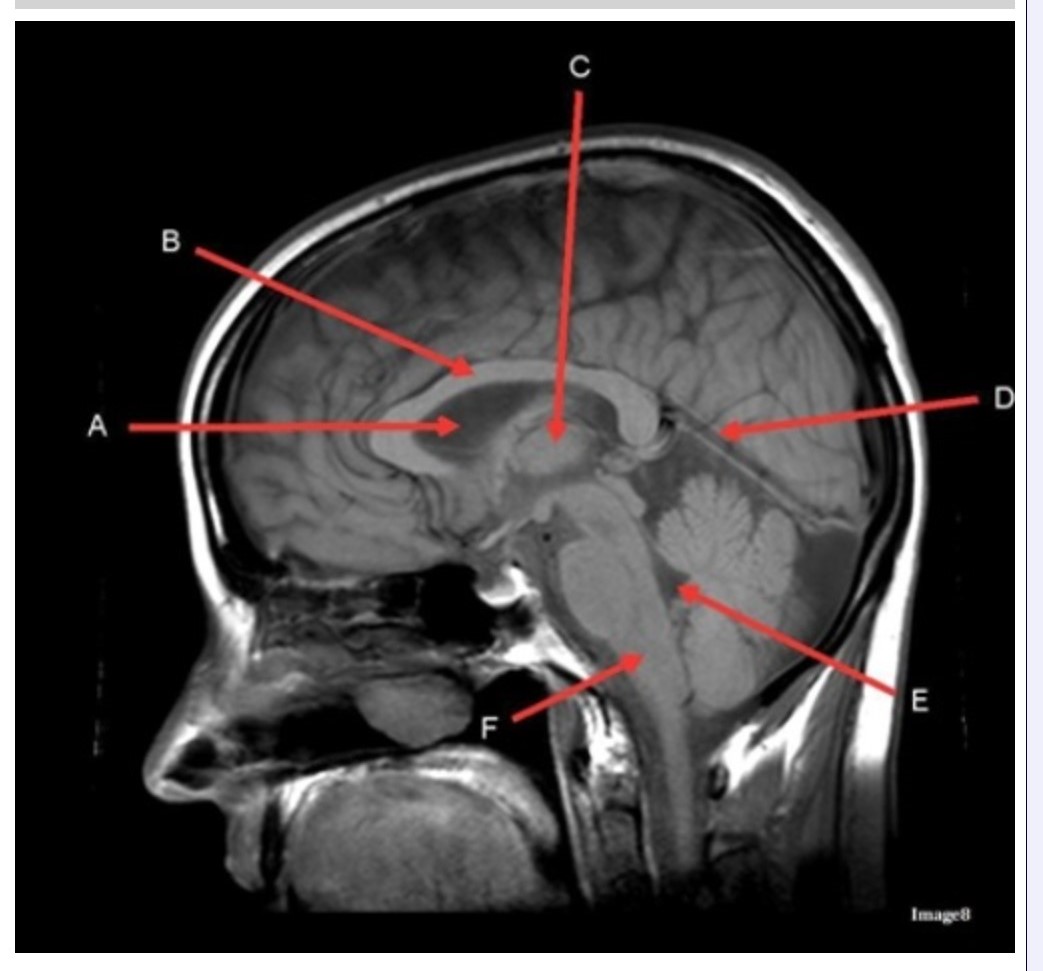

Letter C in Image 8 is pointing to:

A. Tentorium

B. Corpus callosum

C. Thalamus

D. Fourth ventricle

E. Medulla oblongata

Letter F in Image 8 is pointing to:

A. Tentorium

B. Cerebellum

C. Thalamus

D. Fourth ventricle

E. Medulla oblongata

Letter E in Image 8 is pointing to:

A. Tentorium

B. Cerebellum

C. Thalamus

D. Fourth ventricle

E. Medulla oblongata

Letter B in Image 8 is pointing to:

A. Tentorium

B. Corpus callosum

C. Hypothalamus

D. Fourth ventricle

E. Medulla oblongata

Letter D in Image 8 is pointing to:

A. Tentorium

B. Cerebellum

C. Thalamus

D. Fourth ventricle

E. Medulla oblongata

Image 8 is an example of a _______ weighted sequence acquired in the _______ scan plane.

A. T1; Axial

B. T1; Sagittal

C. T2; Axial

D. T2; Sagittal